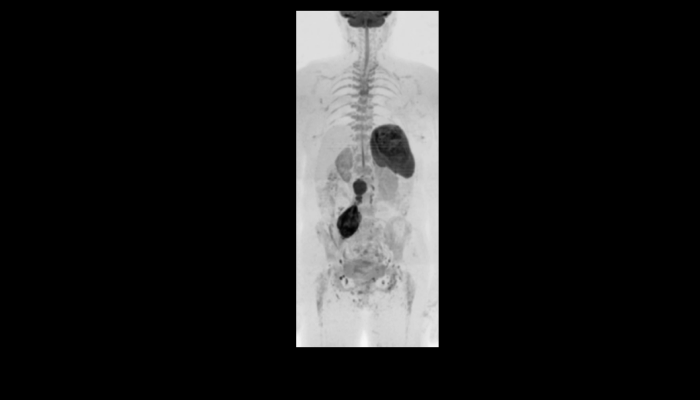

頭部MRI画像 頭部MRI脳腫瘍や脳梗塞、認知症など脳の病気を詳細に評価します。 MRA画像 頭部MRA造影剤を使わずに脳の動脈を描出します。動脈瘤や狭窄を検索します。 脊椎MRI画像 脊椎MRI椎間板ヘルニアや脊柱管狭窄症など脊椎や脊髄の疾患を評価します。 腹部MRI画像 上腹部MRI・MRCP肝臓・胆のう・膵臓・腎臓などの上腹部の重要臓器を詳細に評価します。 乳房MRI画像 乳腺MRIマンモグラフィや超音波と併せて、乳がんを検索や病変の範囲を評価します。 前立腺MRI画像 前立腺MRI前立腺がんを検索します。PSA高値の方はまず前立腺MRIをお勧めします。 子宮・卵巣MRI画像 子宮・卵巣子宮筋腫や子宮体癌、卵巣腫瘍など女性特有の病気を評価します。 膝関節MRI画像 膝関節膝関節の骨や靭帯、半月板を評価します。靭帯断裂や半月板損傷などレントゲンでは評価できない構造も診断できます。 肩関節MRI画像 肩関節肩関節の骨や腱、靭帯を評価します。腱板断裂や腱の断裂などレントゲンでは評価できない構造も診断できます。 心臓MRA 心臓MRA狭心症、心筋梗塞の原因となる冠動脈の狭窄を評価します。造影剤を使用せず、撮影可能です。 DWIBS画像 DWIBS全身のがんを広く検索します。リンパ節や転移の評価にも優れます。